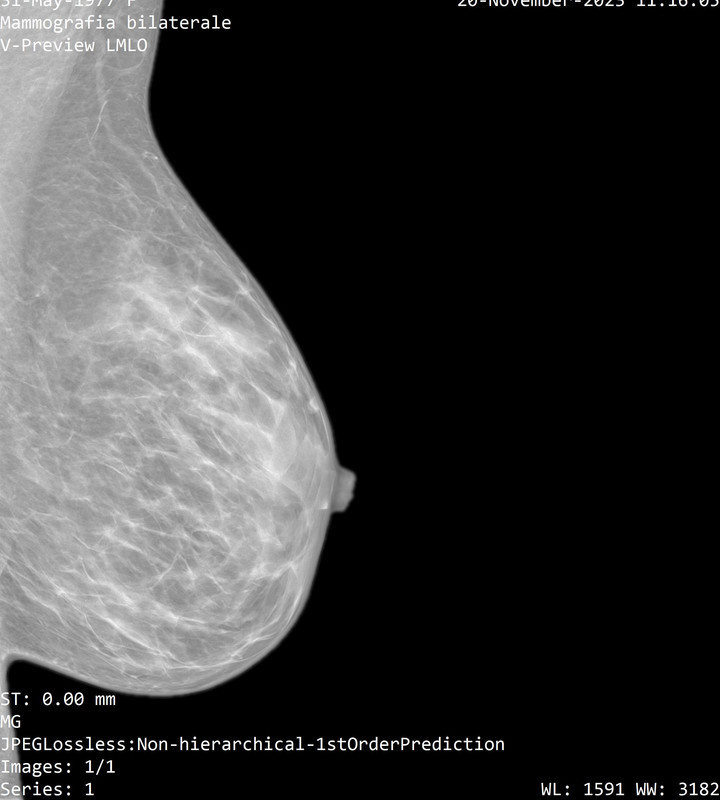

Onestamente non capisco neppure quale sia la mammella destra dalla sinistra...

Il referto dice:

"a dx al passaggio tra i quadranti inferiori e' meglio visibile un focolaio di microcalcificazioni, non riconoscibile con certezza all'ecografia mirata, meritevole di caratterizzazione mediante agobiopsia con sistema VAB sotto guida mammografica